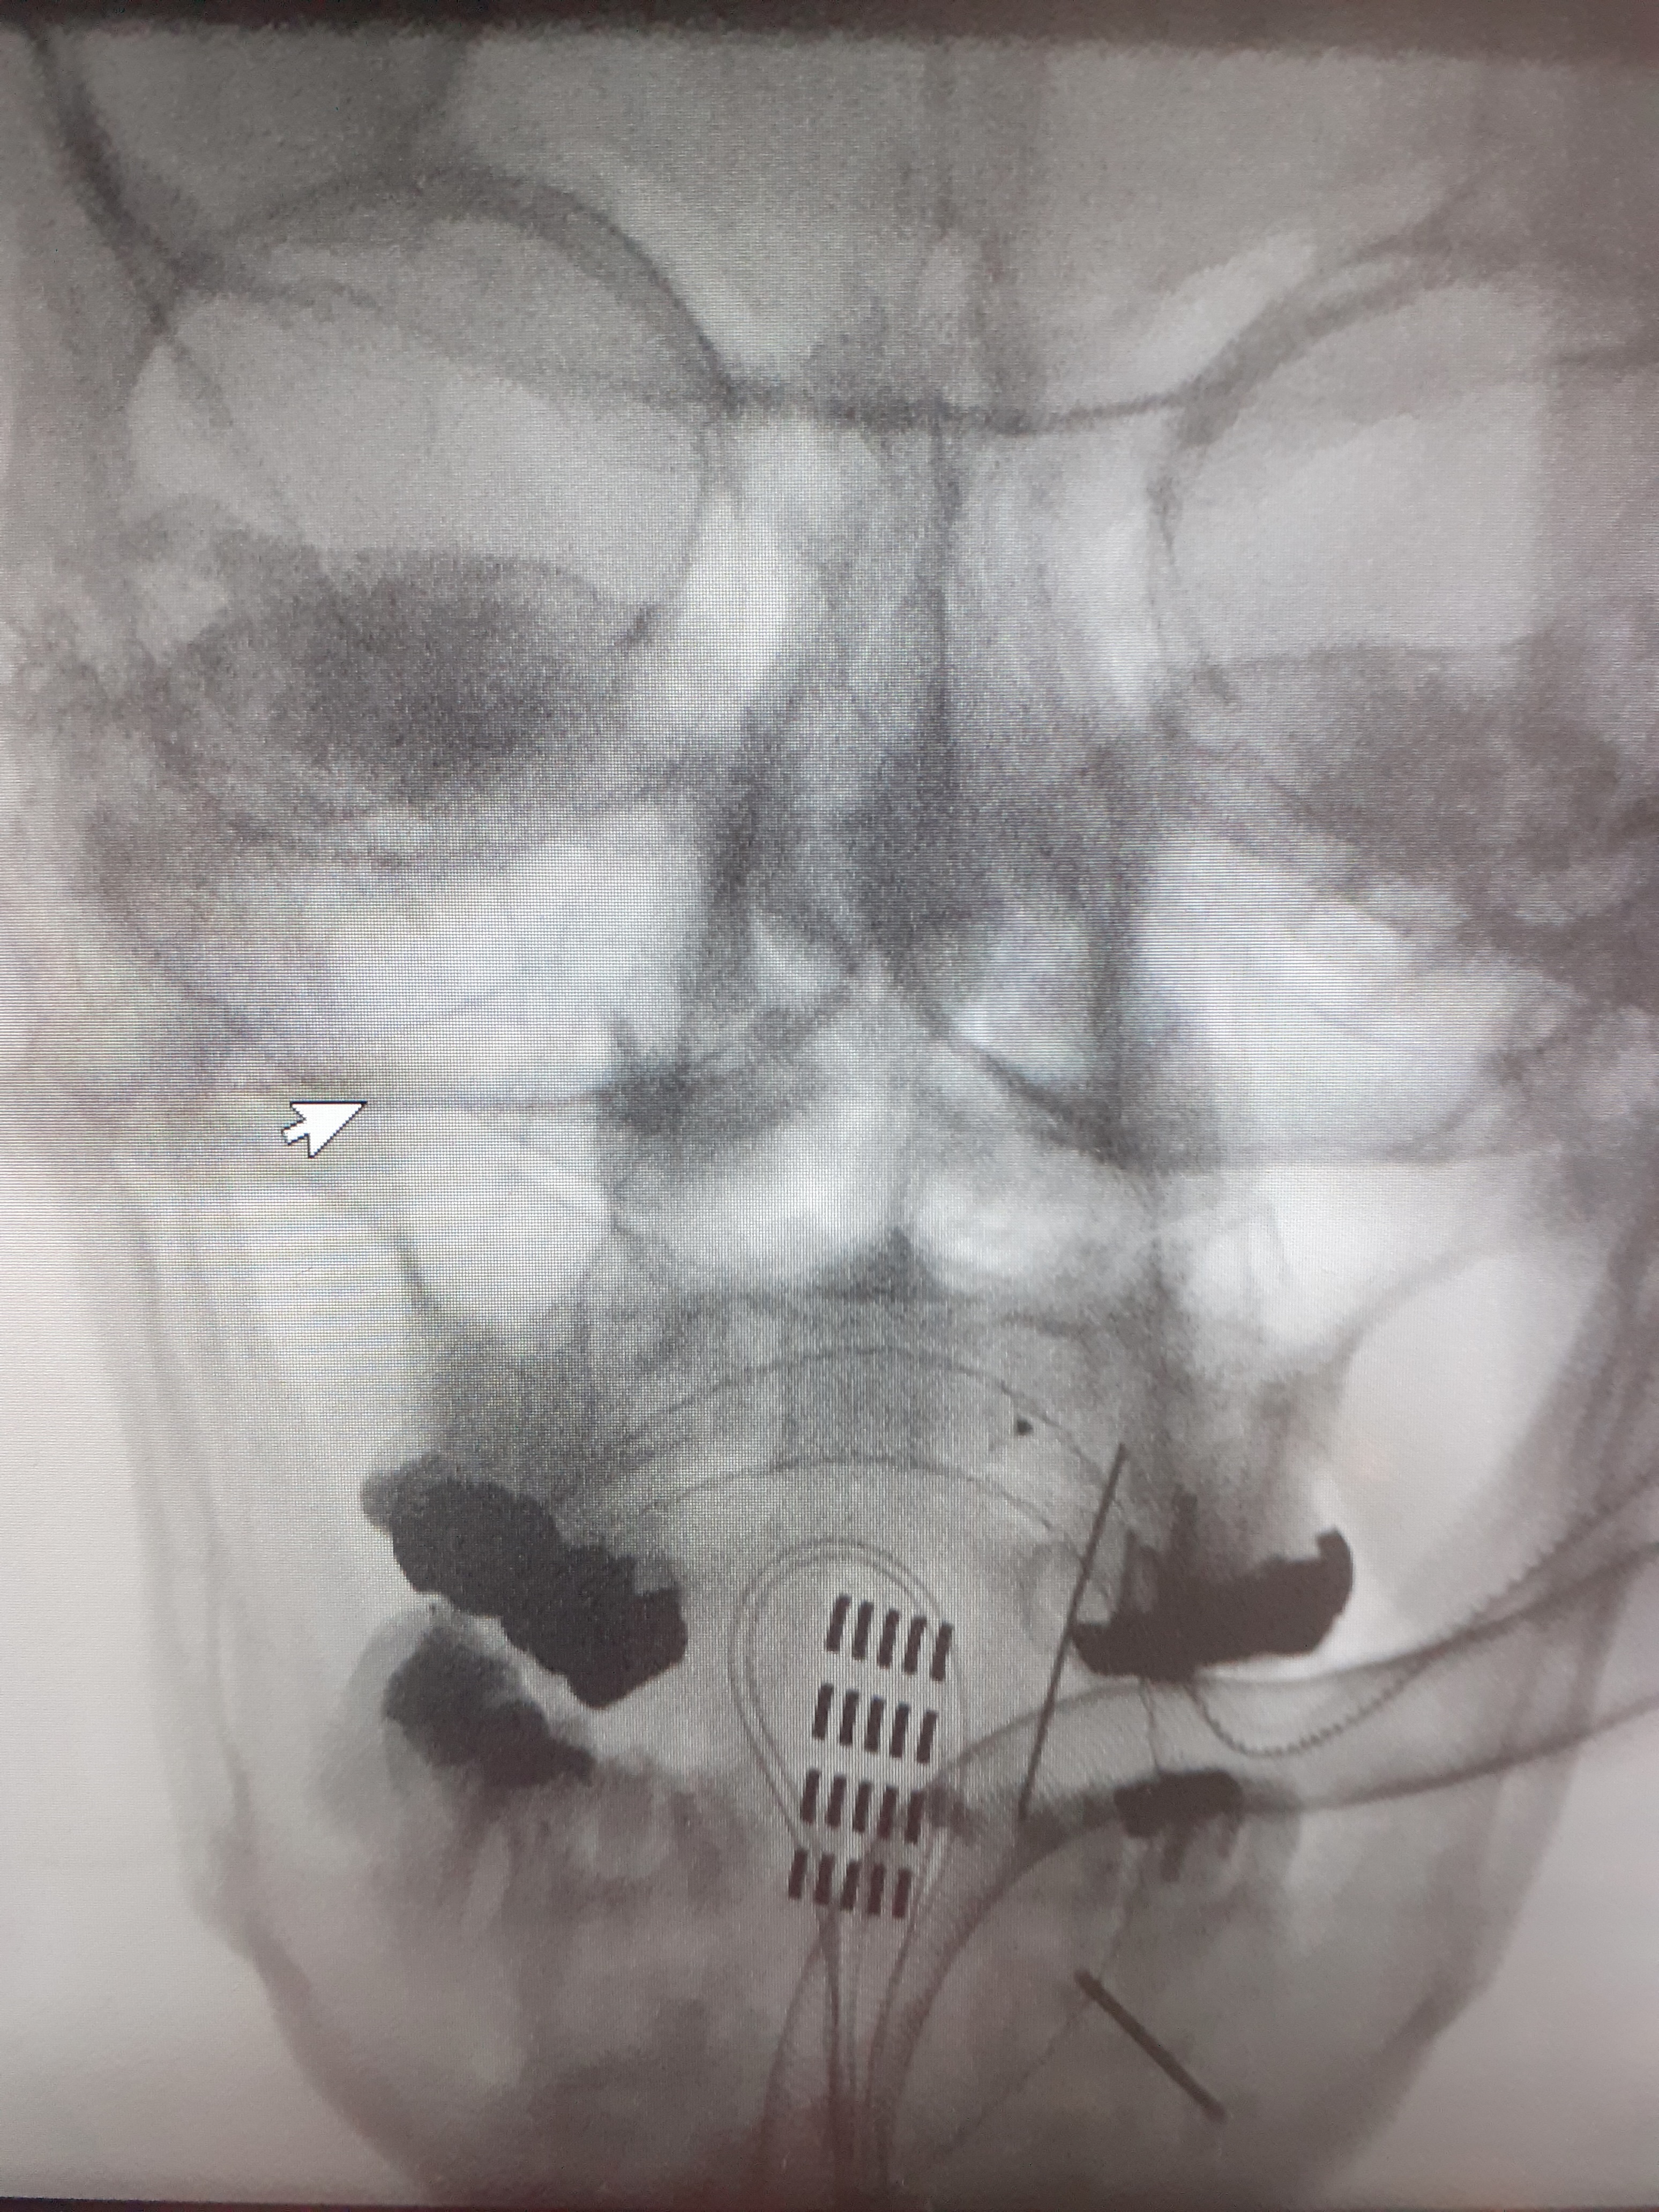

I think I mentioned in my pre-surgery post that I had asked for some pictures of what they were actually doing inside me. I asked again whilst I was at the clinic if the images could be sent over, and I’ve since received them.

The Abbott electrode is not in my mouth as the image suggests, and nor did I have a pair of round glasses on during surgery! Actually, I was unconscious, so who knows if it is a pair of glasses? 😆

The white area next to the electrode in the lateral view is scar tissue that Mr Mundil was worried about removing more than he had because it was extremely hard, and too close to the spinal cord, thus there was risk of damaging the cord. It is unfortunately this scar tissue that is blocking the closed-loop capability as the device needs to receive signals back from the lower end of the paddle to close the loop. They tried sending the input signals to the lower end so that the responses could be picked up from the top where it is close to the cord, but it was not providing any benefit without increasing the power to inappropriate levels.